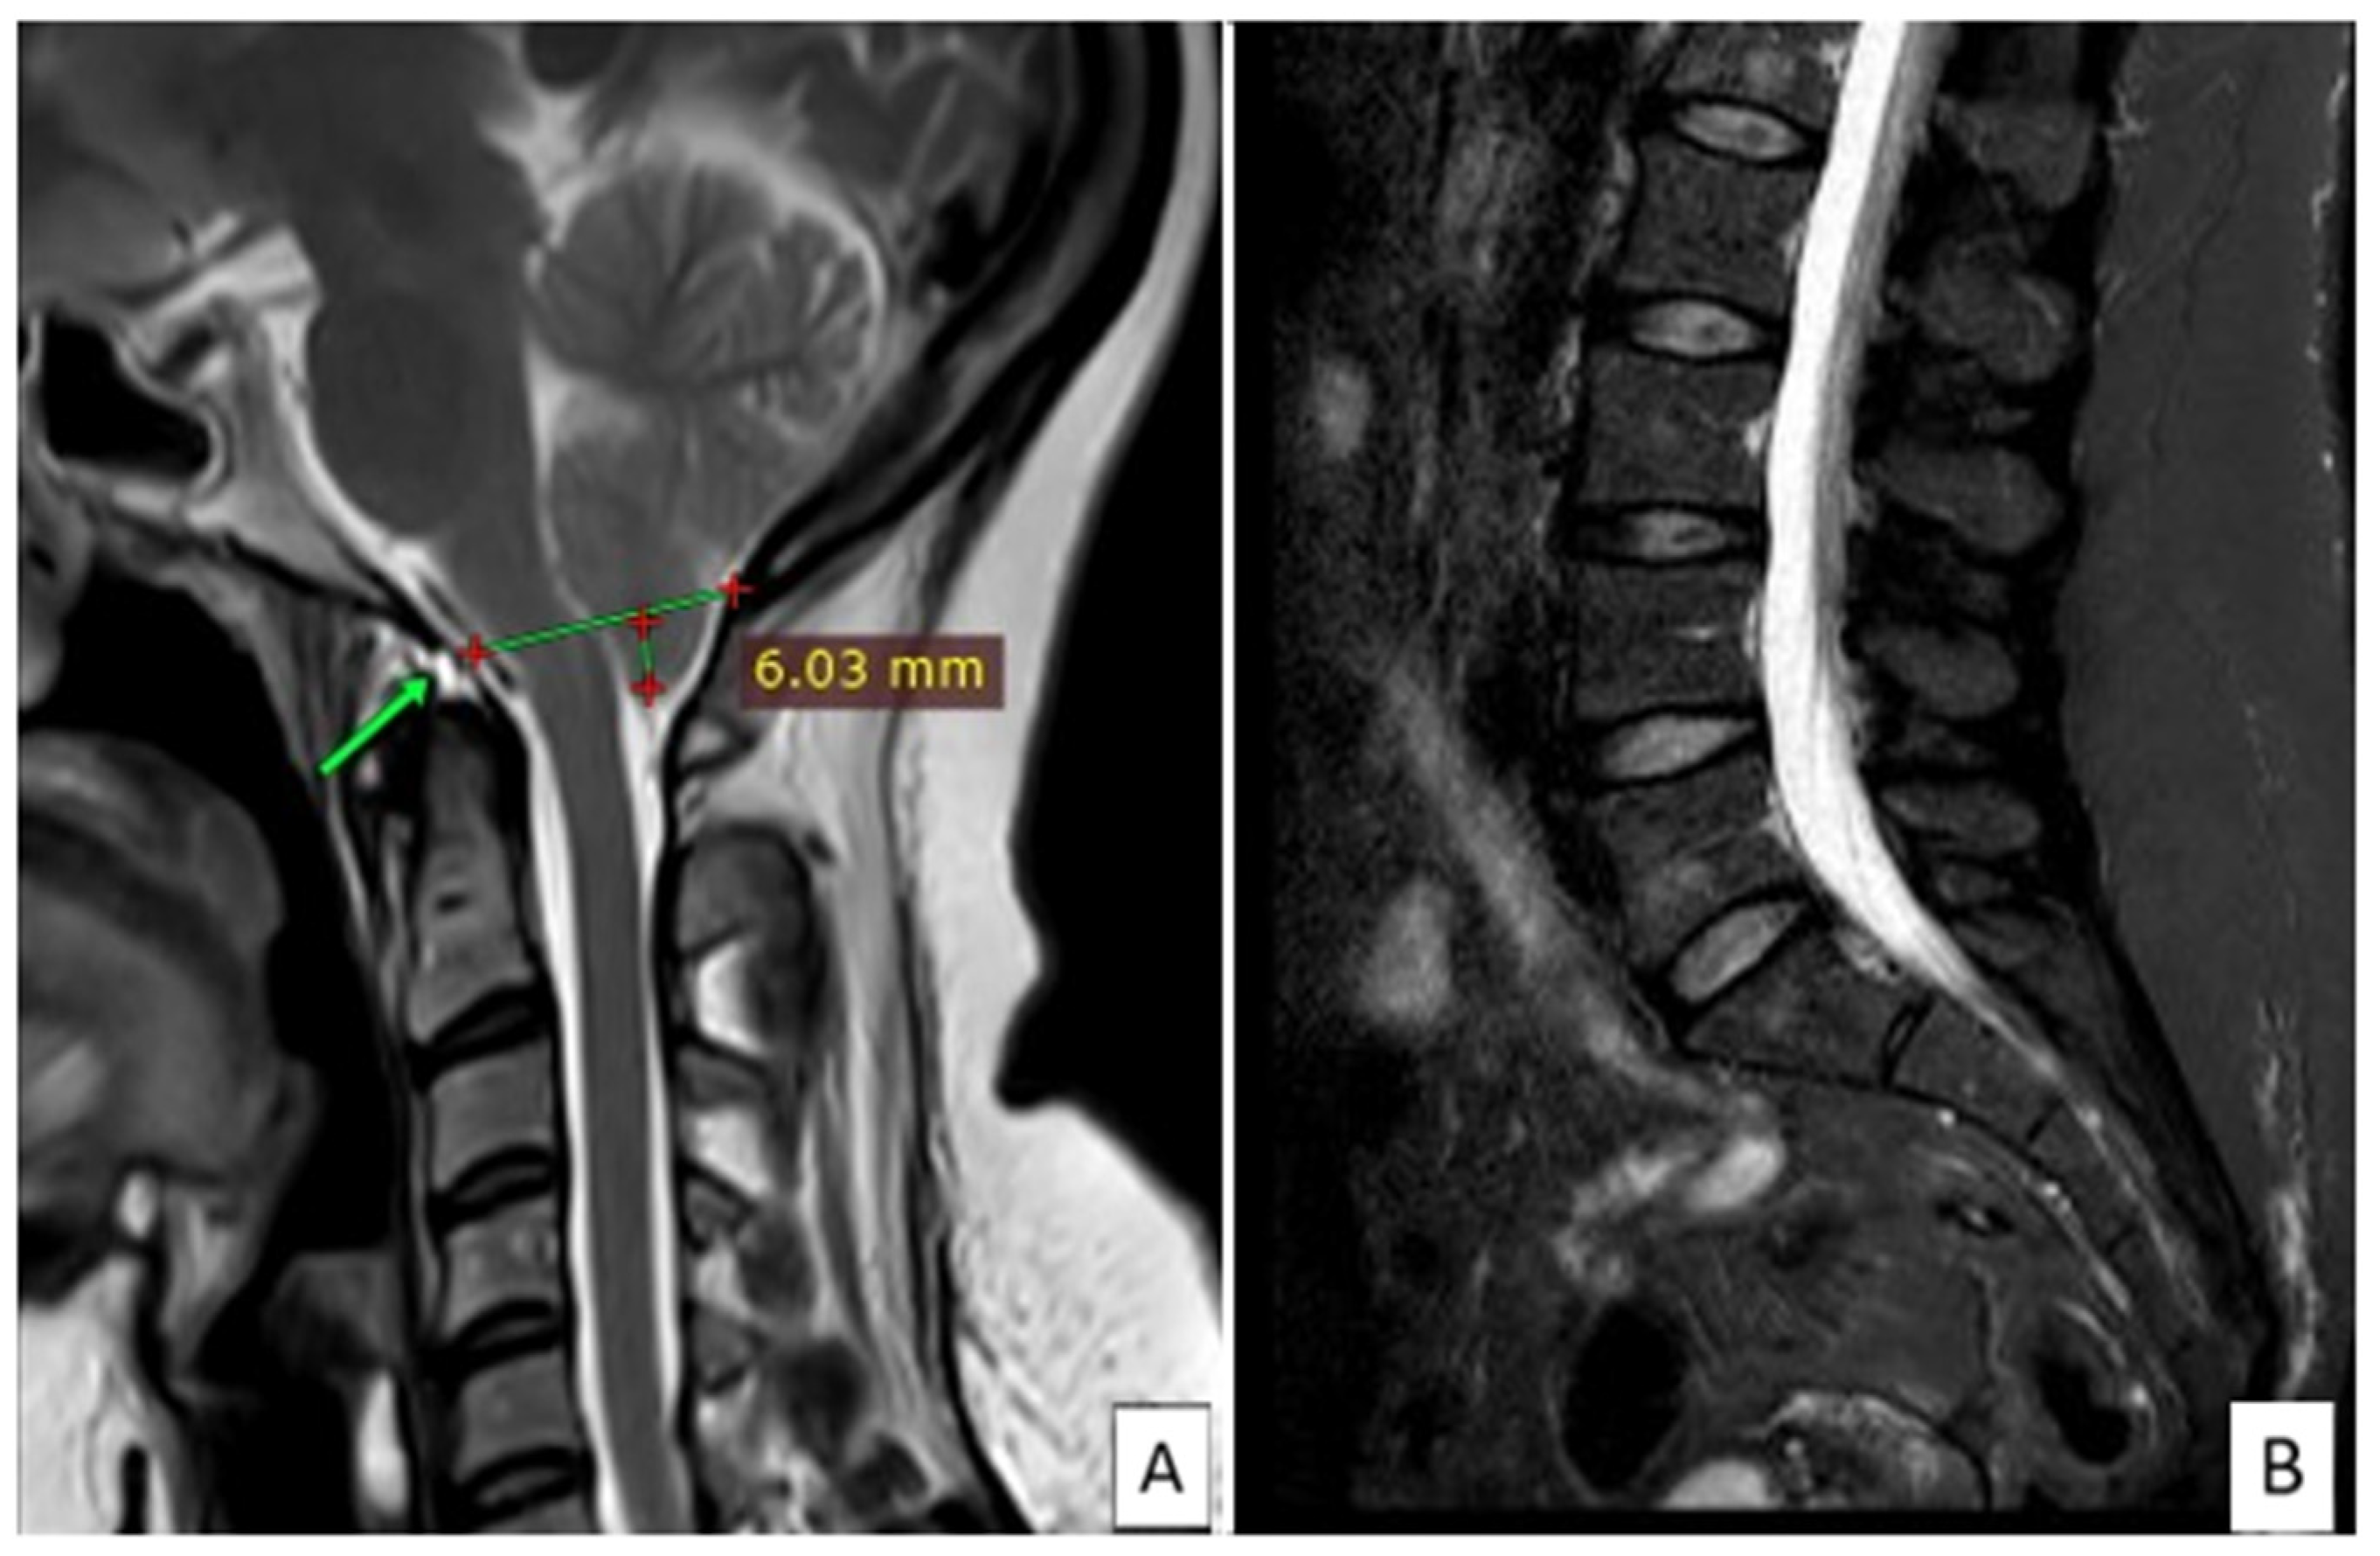

2. Case Presentation